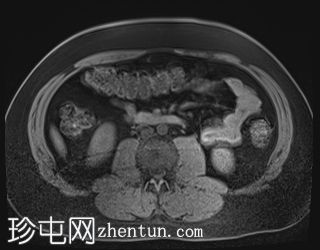

轴位T1加权像

同相位序列

T1低信号,T2低信号为主的脾脏肿块,内部可见T2高信号分隔,呈进行性强化。肿块中央可见星状瘢痕。

脾脏硬化性血管瘤样结节性转化(SANT),9.8 cm肿块

顾名思义,脾脏硬化性血管瘤样结节性转化(SANT)是一种纤维性血管病变。本病例展示了SANT的一些典型影像学特征,包括边界清晰的病灶,中央可见瘢痕,以及呈放射状进行性强化。这些特征使得术前MRI诊断较为明确。尽管SANT是一种良性病变,但大多数患者仍需行脾切除术以明确病理诊断。